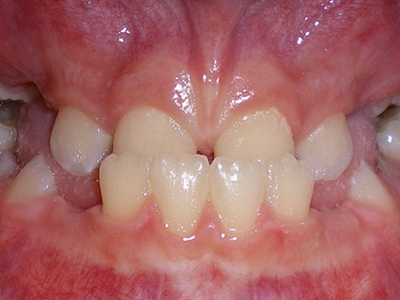

牙龈炎是发生于牙龈组织的炎症,患者可出现牙龈出血伴肿胀、发红、正常形态改变和偶尔不适等症状。本病主要由口腔卫生状况差导致,包括口腔不洁、牙菌斑等,诊断依据临床检查,治疗包括专业牙齿清洁和加强家庭口腔卫生。

牙龈炎可先引起牙齿与牙龈之间的沟(龈沟)加深,然后牙龈充血,炎症围绕一个或多个牙齿,伴牙龈乳头肿胀和易出血。一般无痛,可自行消退,也可维持轻度炎症数年。